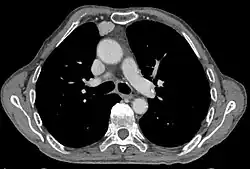

Hinweise auf ein Thymom ergeben sich schon im Röntgenbild des Brustkorbes bei Vorliegen einer unklaren vorderen mediastinalen Raumforderung. Es zählt zu den mnemotechnisch oft zitierten vier T’s in der Differentialdiagnostik der vorderen mediastinalen Raumforderungen (Teratom, Thymom, Glandula thyroidea und „terrible lymphoma“). Zur Standarddiagnostik gehört die Computertomographie (CT). Zur Unterscheidung von gutartigen und bösartigen Tumoren ist stets die Entnahme einer Gewebeprobe (Biopsie) und deren feingewebliche Untersuchung nötig.